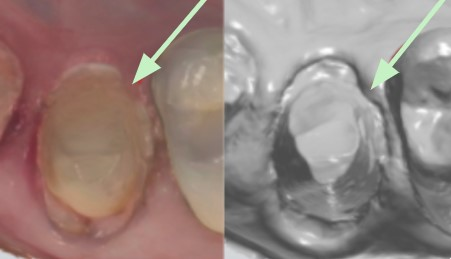

Visibilidad del margen

• Visibilidad completa requerida - Asegúrese de que todo el margen alrededor del diente preparado sea visible en el escaneo.

• Vista sin obstrucciones - Verifique que no haya sangre, tejido, cordón o pasta obstruyendo la vista.

Uso de la herramienta de recorte

Si hay obstrucciones, elimínelas del escaneo utilizando la herramienta de recorte. Después de recortar, ajuste según sea necesario y vuelva a escanear el área. A continuación se muestra un ejemplo de los pasos que realizaría al usar la herramienta de recorte para tejido sobre un margen.

• Tejido sobre el margen

• Recortando el área afectada

• Colocación de cordón y reescaneo